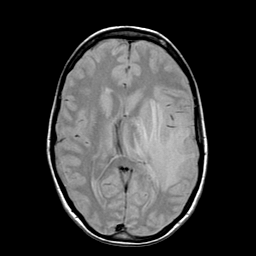

Metastatic bronchogenic carcinoma: proton density-weighted MR -- Slice #12

[Home][Help][Clinical] Slice 12